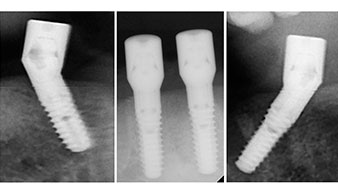

Un CT Scan à faisceaux coniques tridimensionnel (CBCT, Planmeca) a été réalisé au préalable afin de réduire les risques. Il a révélé une qualité et une quantité d'os disponible suffisante pour l'intervention chirurgicale et la restauration immédiate par la méthode All-on-four. En suivant le protocole de ce concept, les implants sont insérés au niveau de 35, 32, 42 et 45 en inclinant les implants distaux jusqu'à 45°, le profil d'émergence se déplace ainsi vers l'arrière et produit un polygone de stabilisation plus large (Fig. 3).

Le protocole chirurgical préconisé pour les implants utilisés (SKY, Bredent Medical) précise une vitesse de rotation de 1.200 tr./min. pour le pré-forage (Fig. 7 - 9).

Ceci correspond à la position suivante prédéfinie dans l'Implantmed. Nous voyons ici le contre-angle W&H tenu à un angle de 45° par rapport à la crête dans la région de 45 afin de préserver le nerf mentonnier. Le trou mentonnier sert de repére anatomique à tous les forages de cette région. Les forages suivants ont été effectués à la vitesse réduite de 300 tr./min. (Fig. 10 et 11).

Le prochain réglage programmé est destiné à la mise en place des implants. Dans notre cabinet, nous appliquons généralement un couple de 32 Ncm pour cette phase (Fig. 12 et 13).

Les piliers angulés (35°) ont été vissés pour compenser la divergence des implants distaux. Ainsi, le profil

d'émergence de tous les implants doit être le plus perpendiculaire possible par rapport au plan occlusal. Il s'agit

d'une condition préalable à la pose en occlusion de la prothèse provisoire puis permanente (Fig. 15 et 16).